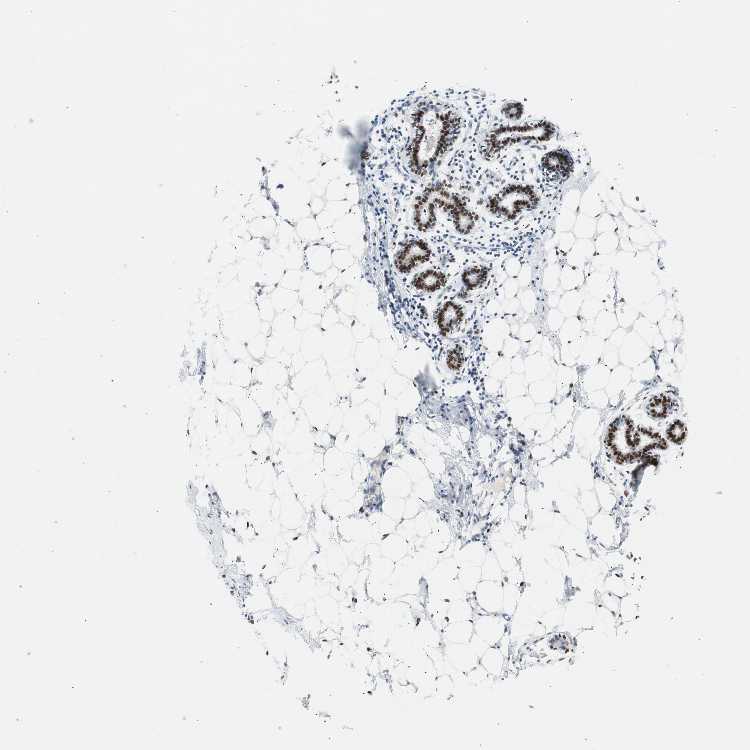

BREAST - Antibody stainingi

Antibody staining in the annotated cell types in the current human tissue is reported as not detected, low, medium, or high, based on conventional immunohistochemistry profiling in selected tissues. This score is based on the combination of the staining intensity and fraction of stained cells.

Each image is clickable and will lead to virtual microscopy that enables deeper exploration of all samples and also displays staining intensity scores, fraction scores and subcellular localization as well as patient and tissue information for each sample.

Antibody CAB004213

Adipocytes Medium

Glandular cells High

Myoepithelial cells High